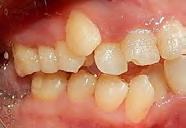

En la Figura 3 se muesta clase III molar y canina, el overjet y overbite negativos, en la Figura 4 las líneas medias coincidentes, la mordida abierta anterior, en la Figura 5 la clase III molar y canina, overjet y overbite negativos, en la figura 6 se ven formas de los arcos ovales, el apiñamiento severo superior e inferior.

Figura 3. Lateral derecha. Figura 4. Frente intraoral. Figura 5. Lateral izquierda. Figura 6. Intraorales oclusales.